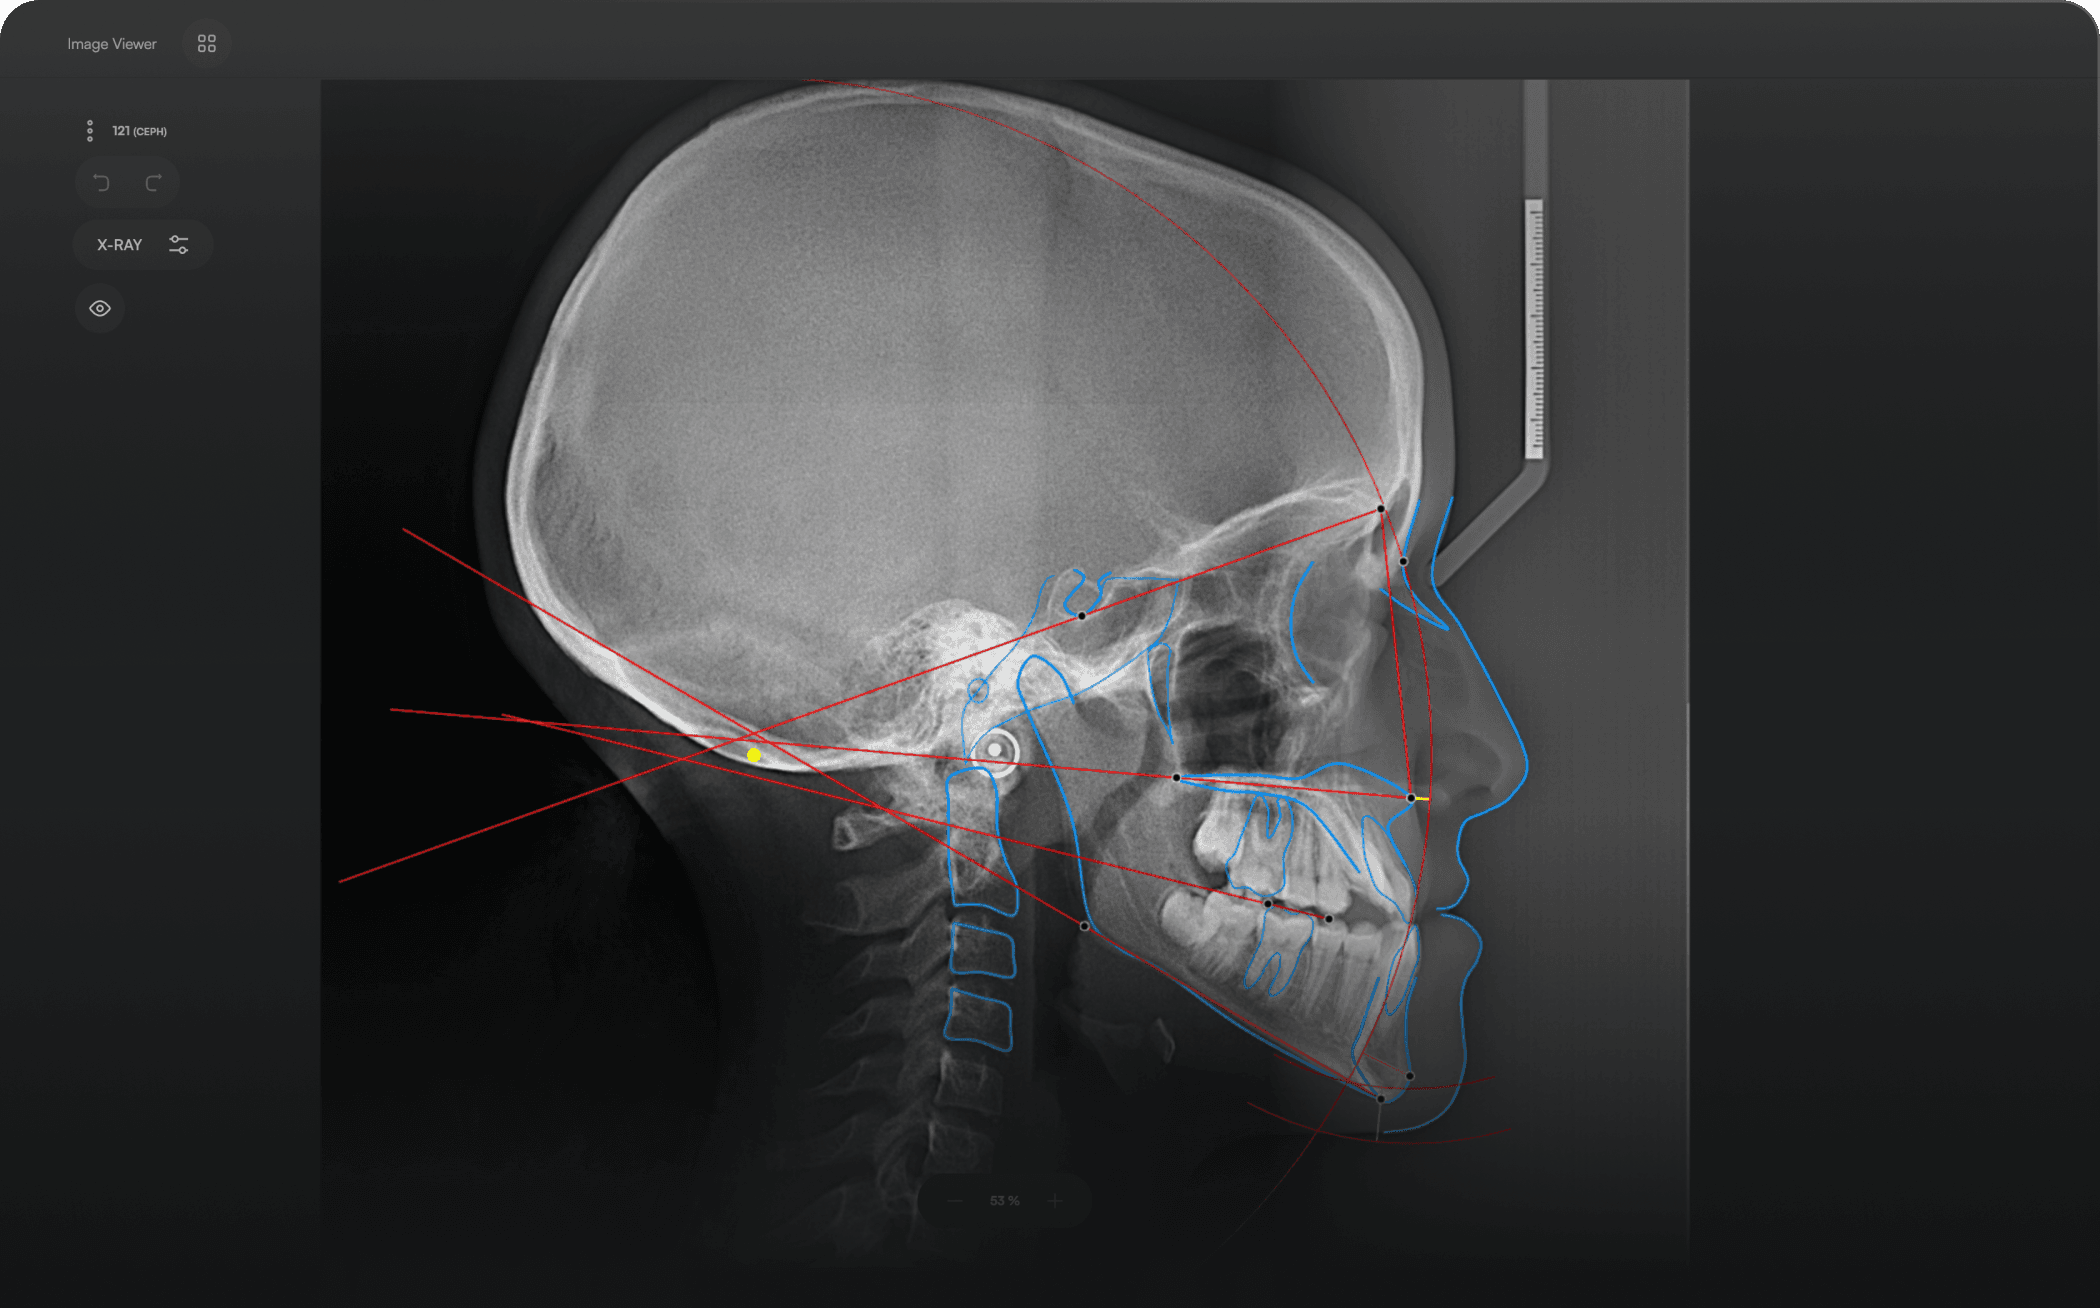

Diverse Analysis

Access automated studies like Steiner and Jefferson to assist in clinical assessment and enhance case evaluations.

Experience a comprehensive assessment of skeletal, dental, and soft tissue discrepancies.